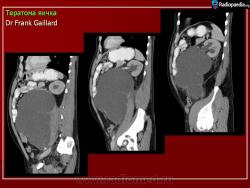

2.

Из литературных источников.